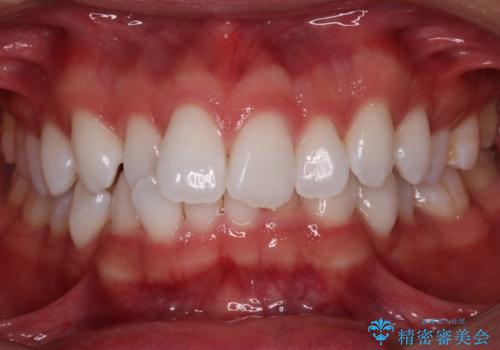

少しスペースクローズに時間がかかりましたが、MIを用いたワイヤー矯正で

主訴である出っ歯と叢生が改善されました。口も閉じやすくなり、スッキリとした口元になりました。